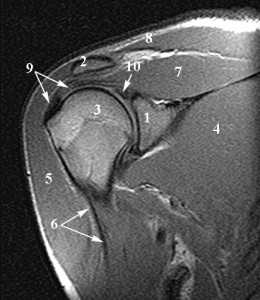

Анатомия плечевого сустава. Т1-зависимая МРТ в корональной плоскости. Обозначения: 1 –суставная (гленоидная) впадина, 2 – ключица, 3 –головка плечевой кости, 4 – подлопаточная мышца, 5 – дельтовидная мышца, 6 – длинная головка сухожилия двуглавой мышцы плеча, 7 – надостная мышца, 8 – трапецевидная мышца, 9 – сухожилие надостной мышцы, 10 – верхняя губа.